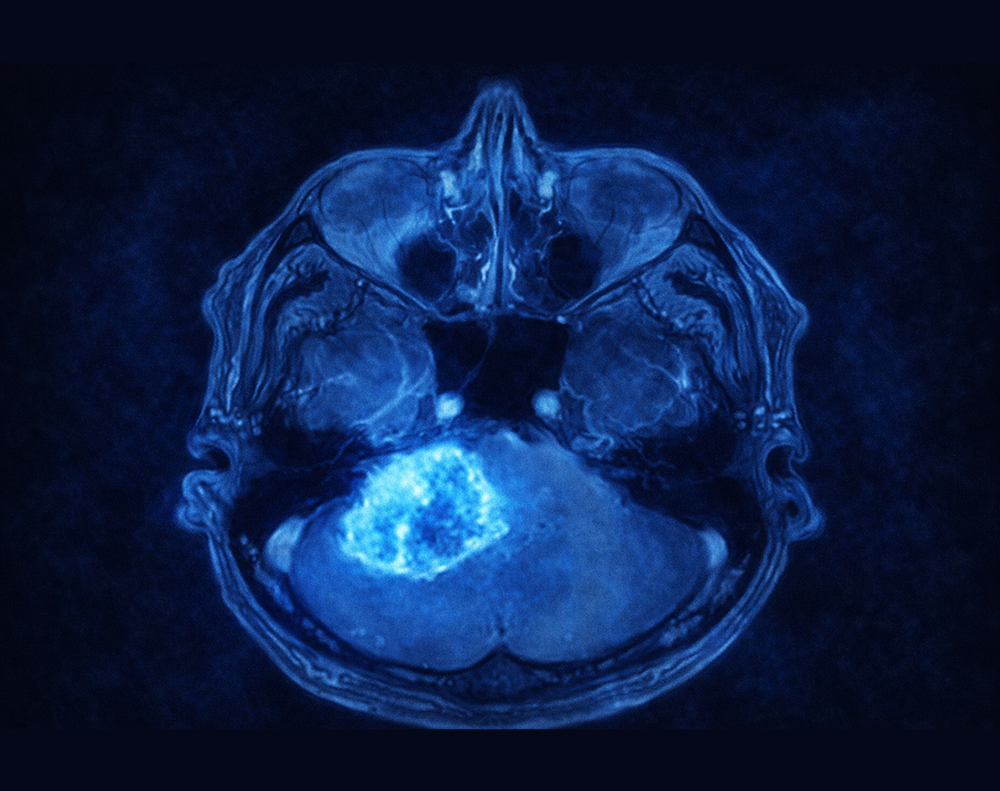

La resonancia magnética es el estudio apropiado para estudiar un schwannoma. Estos tumores generalmente captan medio de contraste de manera regular, aunque pueden presentar degeneración quística. Debido a su crecimiento en las vainas de los nervios, por fuera del cerebro, estos tumores suelen producir un desplazamiento del cerebro normal. A partir de la compresión o efecto de masa, es que se define el tratamiento del paciente.